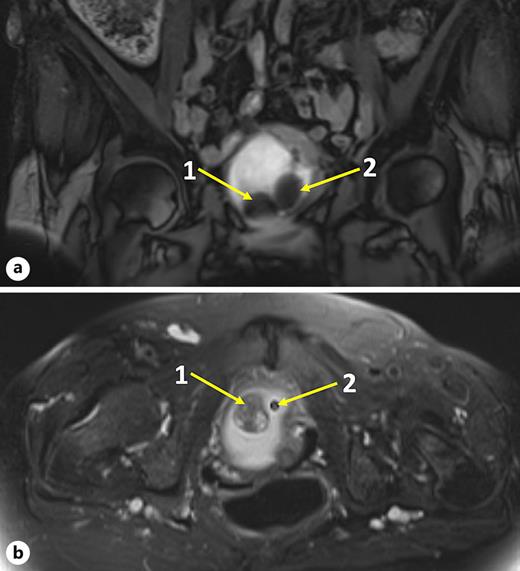

Physical examination revealed no flank masses. Abdominal ultrasound raised the suspicion of a bladder lesion. Urinalysis revealed no white cells or bacteria in the stained urinary sediment. A magnetic resonance imaging of the pelvis and abdomen revealed a sessile bladder mass (2.8 cm) at the bladder trigone on the right side, without perivesical infiltration or regional lymphadenopathy described as leiomyoma, as shown in Figure 1. Cystoscopy revealed the suspected bladder leiomyoma and an obstructed anterior bladder neck with a large mass located from a “7 o’clock” to “11 o’clock” area. Typical redness of the tissue was detected because of the indwelling urinary catheter. The photodynamic diagnosis was negative, as shown in Figure 2b.

MRI of the pelvis. a T1. b T2 sagittal section. In both panels, “1” indicates the 2.8 × 2.4 × 2.0 cm suspected lesion and “2” indicates the urinary catheter.